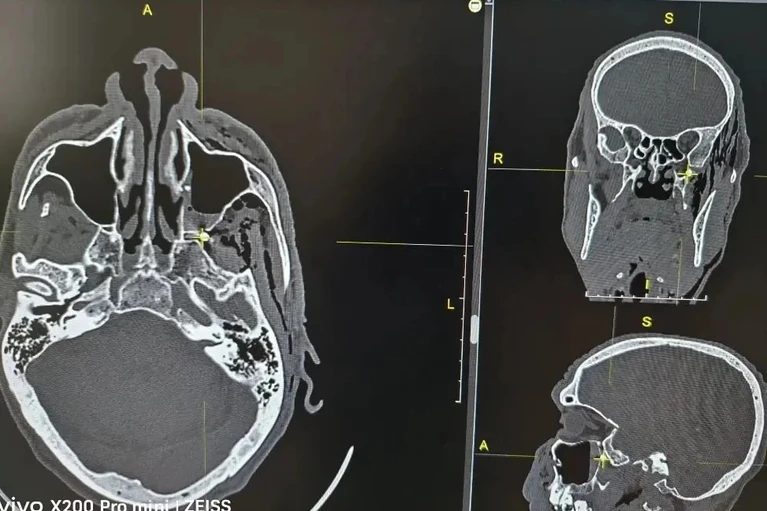

ЧП случилось на даче пострадавшего – сосед выстрелил орчанину в голову из пневматики. Раненого доставили в хирургический стационар Городской больницы Орска. Обследование показало страшную картину: пуля пробила переднюю и заднюю стенки верхнечелюстной пазухи и застряла в так называемой крыло-небной ямке.

Это место внутри черепа за верхней челюстью похоже на сложный коммутатор. Там сходятся нервы и сосуды, а пять отверстий ведут в глазницу, рот, нос, череп и под скулу. Узел, который там находится, управляет чувствительностью и работой желез в носу, небе и глотке. Сплошные сосуды. Любое неловкое движение инструментом – и может открыться смертельное кровотечение.